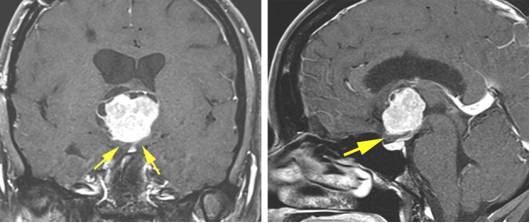

图7. 图示脉络丛、透明隔静脉和丘纹静脉的手术解剖。通过脉络膜裂前部一小段分离扩大室间孔的关键操作是在隔静脉汇入丘纹静脉之前切断。穹隆和丘纹静脉必须被保留。尽管笔者更愿意沿丘脑侧分离脉络裂而不是沿穹隆一侧分离来达到保护穹隆的目的,但是脉络裂的实际解剖更可能提示最合理的分离界面。换句话来讲,笔者并不推荐固定的分离策略(总是沿着丘脑脉络带或者穹隆带)。穹隆构成室间孔前壁的边界,在器械移动过程中应该注意保护。

图8. 图示经室间孔经静脉经脉络膜入路的术中视野角度(绿色区域)和视角盲点(红色区域)。